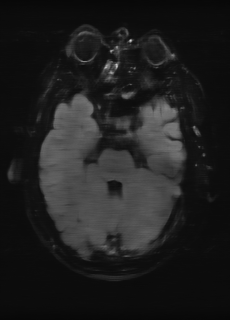

As we observe from the right image in Fig. 2, our BRM, both from MIMO and SISO settings, predicts the performance of dedicated models with a high correlation. We further choose the best three , and perform the last stage of fine-tuning accordingly to (6). A visual evaluation on real data is shown in Fig. 3. For simulated data, please refer to the Supplemental Material section.

Base on the best performing , we perceive that among , , and FLAIR, the results are best when is sampled the most. We suggest that this makes intuitive sense as images provide the best contrast out of the three sequences, which can compensate for the details lost in other images. The same observation can be made on the simulated data, where both and FLAIR show good contrast. When the time setting is changed to non-uniformity, we can see that our search for the best sampling strategy reflects the change. is sampled more as a result of faster acquisition time, while is still sufficiently sampled.

(a) 34.38/0.9371

(a) 34.38/0.9371

|

(b) 42.42/0.9883

(b) 42.42/0.9883

|

(c) 44.60/0.9920

(c) 44.60/0.9920

|

(d) 45.50/0.9940

(d) 45.50/0.9940

|

(e) PSNR/SSIM

(e) PSNR/SSIM

|

|

(f) 29.74/0.8903

(f) 29.74/0.8903

|

(g) 36.25/0.9734

(g) 36.25/0.9734

|

(h) 36.42/0.9752

(h) 36.42/0.9752

|

(i) 37.70/0.9832

(i) 37.70/0.9832

|

(j) PSNR/SSIM

(j) PSNR/SSIM

|

|

(k) 39.89/0.9311

(k) 39.89/0.9311

|

(l) 43.94/0.9864

(l) 43.94/0.9864

|

(m) 44.74/0.9883

(m) 44.74/0.9883

|

(n) 45.49/0.9894

(n) 45.49/0.9894

|

(o) PSNR/SSIM

(o) PSNR/SSIM

|